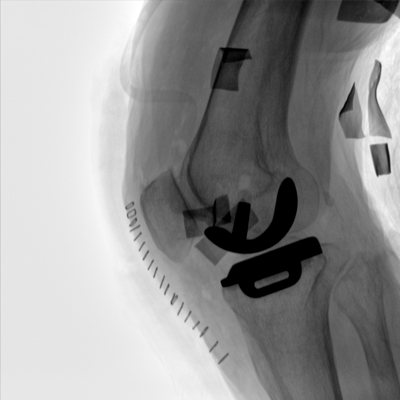

大尺寸動(dòng)態(tài)平板探測(cè)器,高DQE、低噪聲、圖像清晰。采用多分辨率圖像增強(qiáng)處理技術(shù),不同部位不同圖像處理算法,滿足客戶多樣化的需求。

采用智能變頻脈沖透視技術(shù),優(yōu)化圖像質(zhì)量的同時(shí)降低輻射劑量,呵護(hù)醫(yī)患健康

圖形化操控界面設(shè)計(jì):設(shè)有多種人體特征攝影參數(shù),操作簡(jiǎn)便。雙向紅光十字定位系統(tǒng):實(shí)現(xiàn)無射線下的高效定位。信息共享:遵循DICOM3.0格式接口,可無縫對(duì)接云PACS系統(tǒng)。